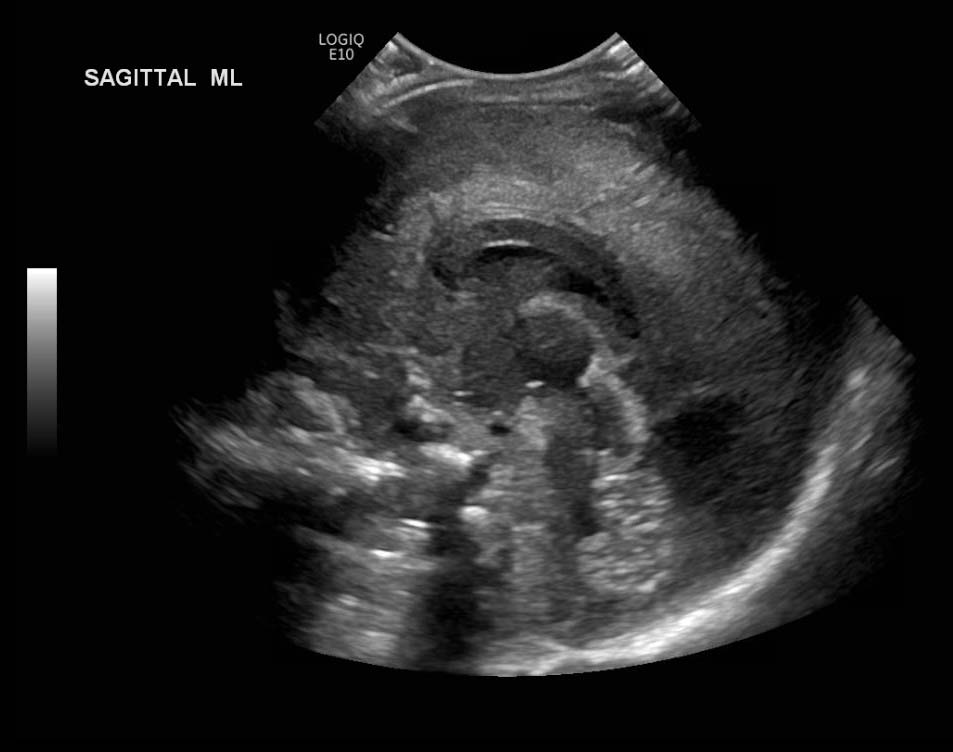

Age: 4 days (born at 24 weeks)

Sex: Male

Indication: Evaluate for germinal matrix hemorrhage

Grade 2 germinal matrix hemorrhage

Sample ReportLeft germinal matrix hemorrhage involving the caudothalamic groove and layering in the occipital horn of the left lateral ventricle without hydrocephalus (grade 2).

No abnormal brain parenchymal echogenicity or extra-axial collections.

Premature sulcation pattern.